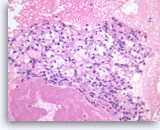

Plasma cell neoplasm,

Pancreas FNA, Direct Smear.

The aspirates show dispersed single cells with a prominent plasmacytoid appearance. The tumor cells vary slightly in size. Rare mitoses are seen.

20X

Plasma cell neoplasm,

Pancreas FNA, Direct Smear.

The aspirates show dispersed single cells with a prominent plasmacytoid appearance. The tumor cells vary slightly in size. Rare mitoses are seen.

20X